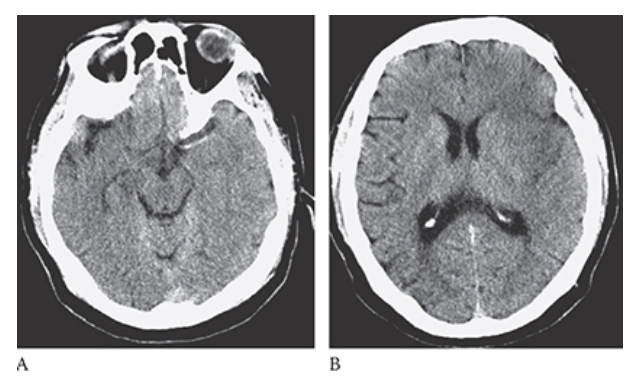

What is A

Glioblastoma Multiforme. Pre-axial CT images show a large peripherally enhancing centrally necrotic mass in the right frontal lobe which is extending across the white matter tracts of the anterior corpus callosum. Note the surrounding edema and mass effect resulting in midline shift.

What is B

Glioblastoma Multiforme. postcontrast axial CT images show a large peripherally enhancing centrally necrotic mass in the right frontal lobe which is extending across the white matter tracts of the anterior corpus callosum. Note the surrounding edema and mass effect resulting in midline shift.